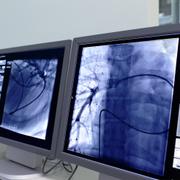

AI används i allt högre grad för medicinska självtester som kan varna för sjukdomar redan innan symtom uppstår, rapporterar AFP. På teknikmässan CES i Las Vegas visades bland annat ett headset som analyserar hjärnsignaler för att upptäcka tidiga tecken på Alzheimers och en app som skannar ögat för att upptäcka cancer.